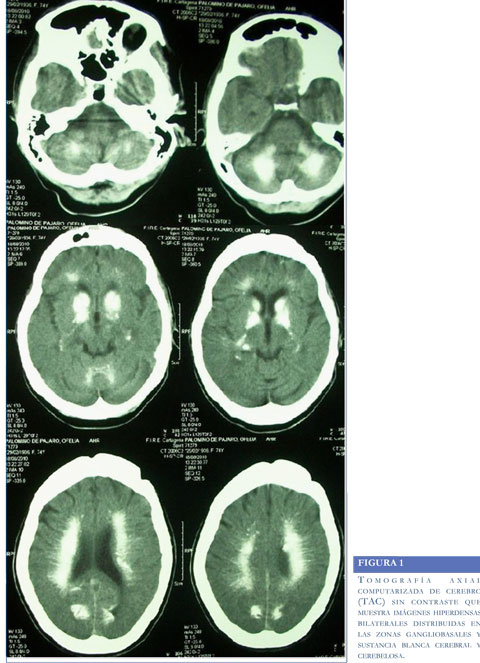

Se solicitaron paraclínicos de función renal, hemograma, ionograma los cuales fueron normales; se realizó TAC cerebral sin contraste que evidenció imágenes hiperdensas calcificas bilaterales sobre los ganglios de la base, sustancia blanca cerebral y cerebelosa. Se apreciaron signos de atrofia cortical leve, sin alteraciones en el sistema ventricular (Figura 1). Con niveles séricos de PTH en 36,5 picogramos/ dl, pruebas de función hepática (ASAT, ALAT), niveles de cortisol de la mañana y pruebas tiroideas en rangos normales. Se realizó además evaluación neuropsicológica cuyos resultados se presentan en la tabla 1.